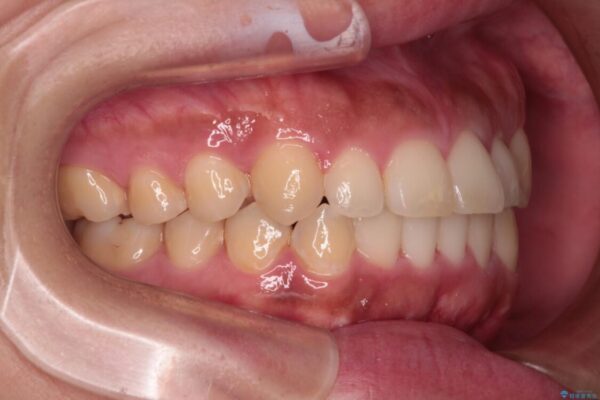

前歯の叢生と八重歯を気にして来院された患者様です。

治療前

• 【モニター】カリエール・ディスタライザーを併用した八重歯のインビザライン矯正 治療前画像